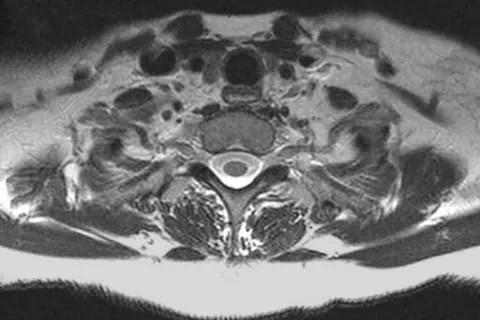

Evaluation of the cervical spine and upper thoracic spine

Here is another example: some imaging centers will perform isolated images of the brachial plexus, sometimes referred to as an MR neurogram.

Again, you can see the brachial plexus is bright, and the background is dark. Similar to the challenges of an isolated MRA, it is almost impossible to know if an adjacent structure is compressing or stretching the brachial plexus, because adjacent structures are intentionally suppressed. The NeoVista® MRI thoracic outlet syndrome test overcomes this limitation.